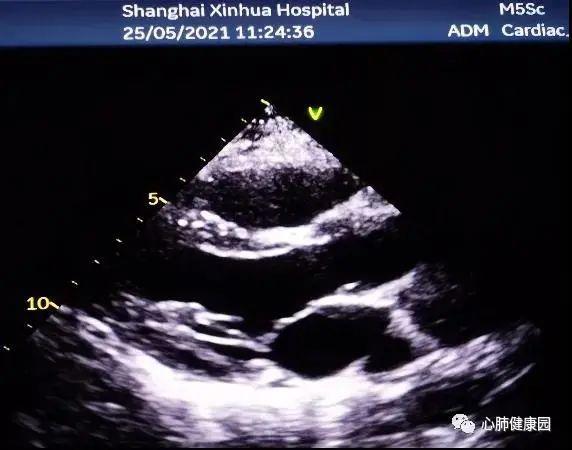

心脏瓣膜疾病之二尖瓣关闭不全的超声特征

二尖瓣狭窄与二尖瓣关闭不全心脏彩超报告解读

超声心动图显示:二尖瓣狭窄,主动脉瓣狭窄伴关闭不全,心脏扩大,考虑为

二尖瓣关闭不全超声

二尖瓣关闭不全

二尖瓣关闭不全图解

二尖瓣关闭不全图片

二尖瓣关闭不全动图

二尖瓣关闭不全示意图